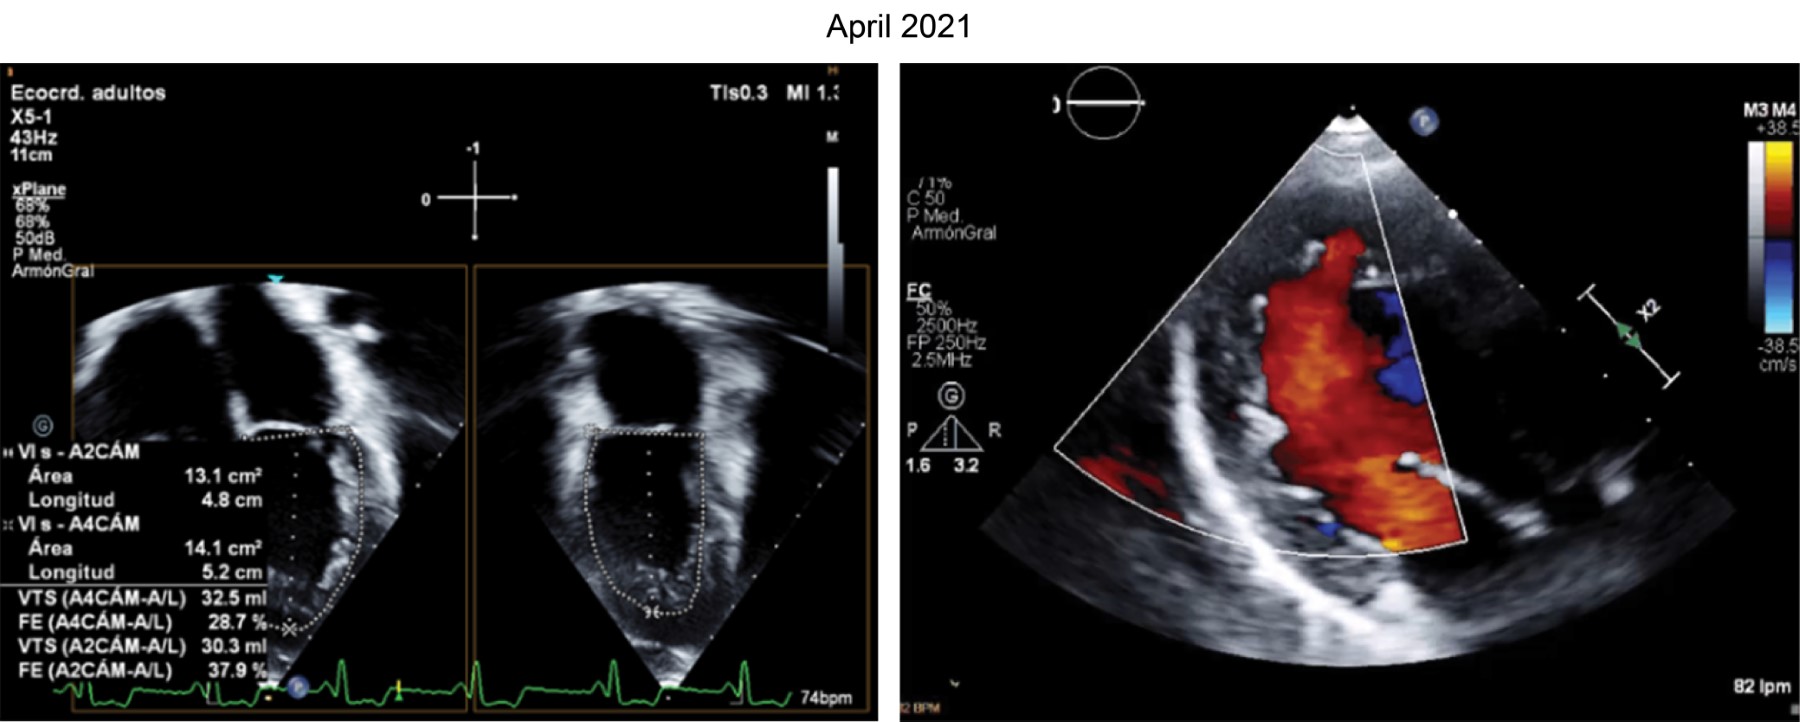

At two years of age, she was readmitted to the hospital due to decompensation of heart failure. Echocardiography revealed dilated cardiomyopathy, mild mitral insufficiency, and dilated left ventricle. MV E/A ratio > 200 mmHg, biplane LVEF 38%, synchrony index 36%, delayed septal contraction in relation to the free wall of 88 ms and 53 ms, RVP 38 mmHg. It was decided to perform pulmonary artery banding. She was discharged after nine days of the procedure due to improvement (Figure 1).

At the age of six years, a new echocardiogram was performed, revealing mild tricuspid regurgitation, mild mitral regurgitation, preserved systolic and diastolic function of the right ventricle, preserved diastolic function of the left ventricle, systolic dysfunction of the left ventricle, and a global strain of -10. The patient continues to be monitored in Cardiology.